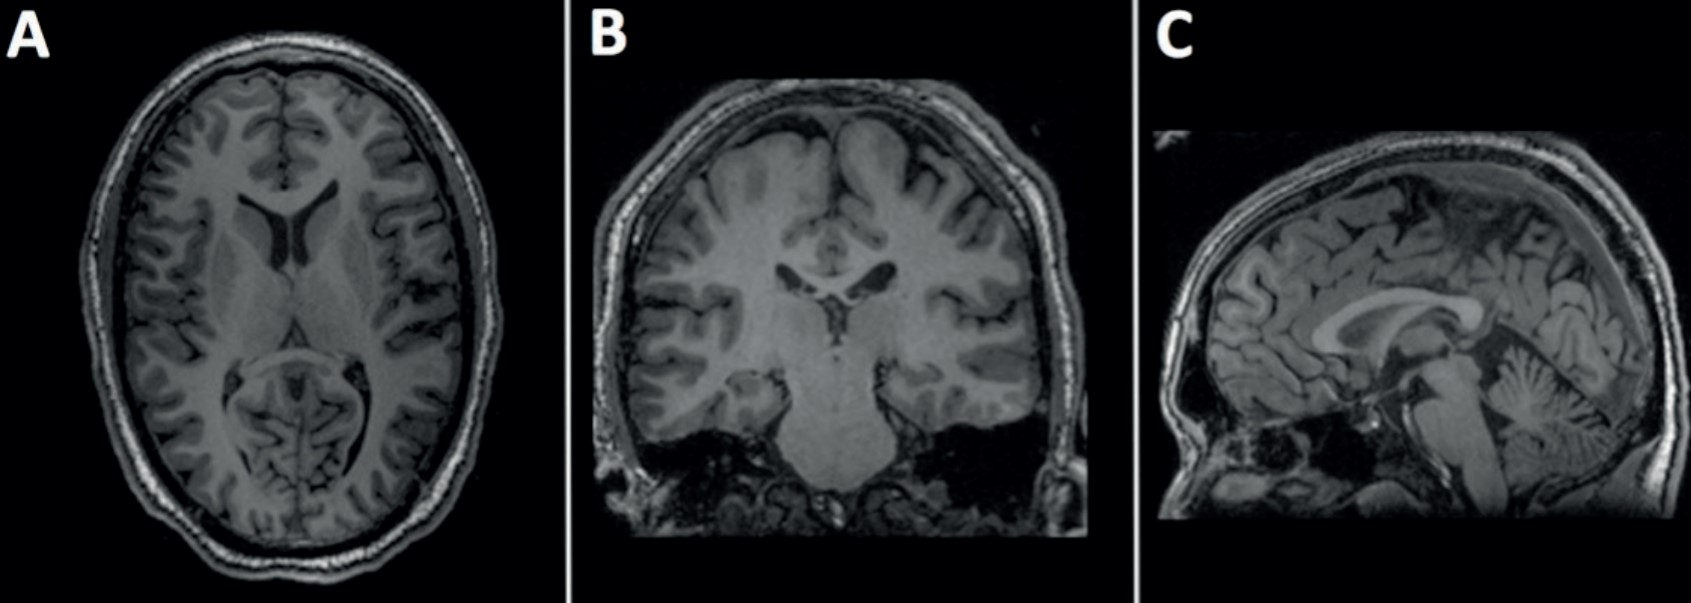

Also for the case of magnetic resonance imaging (MRI), continuous planar images can be stacked and axial (head - toes), sagittal (left-right) and coronal (chest to back) reformats can be reconstructed. An MRI scan is similar to a CT scan in matrix size and pixel gray scale values. Unlike CT, MRI can produce very good contrast resolution between tissues of similar density and thus can diagnose some injuries which remain hidden on CT scans. MRI scans take longer than CTs to acquire, and sometimes the patient’s breathing can make it difficult to acquire a good quality scan.

Current methods for visualization of medical data include the conventional viewing of the volumetric data which is a slice-by-slice viewing method for axial, sagittal and coronal imaging planes or sometimes oblique reformats [67], as shown in Figure 2.4.